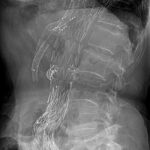

- Den Fenestrerade proximala graftdelen (proximal body) genomlyses först på bordet ovanpå patienten för kontroll av markeringar, etc.

- Därefter förs den fenestrerade graften in över Lunderquist-ledaren (Ipsi-sidan).

- Har graften fenestreringar för ventrala (framåt) bukkärl körs en lateralprojektion (sida) först med kontrast för att positionera hålen i graften rätt höjdledes till dessa framåtgående bukkärl.

- Därefter vinklas C-bågen tillbaka för en frontal-projektion (vinklad frontalt mot njurartäravgångarna) och ny kontrastserie körs för kontroll av njurartäravgångar.